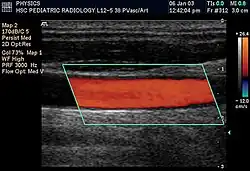

Doppler ultrasonography is widely used in renal ultrasonography. Renal vessels are easily depicted by the color Doppler technique in order to evaluate perfusion. Applying spectral Doppler to the renal artery and selected interlobular arteries, peak systolic velocities, resistive index, and acceleration curves can be estimated (Figure 4) (e.g., peak systolic velocity of the renal artery above 180 cm/s is a predictor of renal artery stenosis of more than 60%, and a resistive index, which is a calculated from peak systolic and end systolic velocity, above 0.70 is indicative of abnormal renovascular resistance).[12]